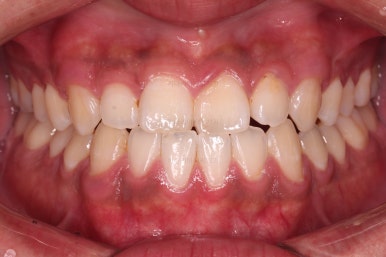

가지런한 느낌, 앞니 뻐드러짐을 좋게 했고요.

교합도 맞춰 위아래가 톱니바퀴처럼 맞물리게 했고, 앞니도 위아래 관계를 잘 맞추고 마무리를 했습니다.

전후 비교해 볼게요.

1년 3개월이라는 비교적 짧은 기간안에 적절한 교합, 심미성 등 여러 가지를 달성했던 만족스러운 치료였습니다.